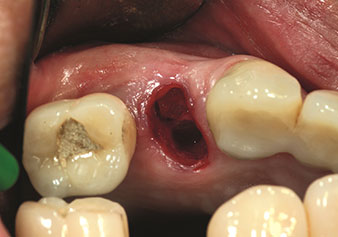

Gestione alveolare

Un’applicazione che viene spesso sottovalutata è l’estrazione atraumatica di radici di denti o frammenti di radici nell’ambito della gestione alveolare. I periotomi sottili, che sono attualmente disponibili in due versioni (EX1 ed EX2 di W&H), possono essere, inoltre, utilizzati per rimuovere con facilità denti che hanno precedentemente subito uno specifico trattamento endodontico o con radici anchilosate. Ne consegue l’estrazione di alveoli in cui i tessuti duro e molle sono entrambi completamente intatti in quanto è generalmente possibile evitare la riflessione.

Ciò pone le basi ottimali per un trattamento con impianto immediato o successivo (Figure 1 e 2 inserite grazie alla gentile concessione del Dott. Torsten Conrad, Bingen a. Rhein).

Foto: © Dott. Torsten Conrad (Bingen am Rhein)